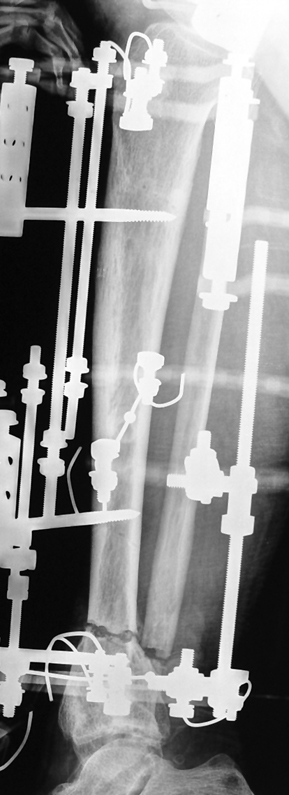

Vaka 2